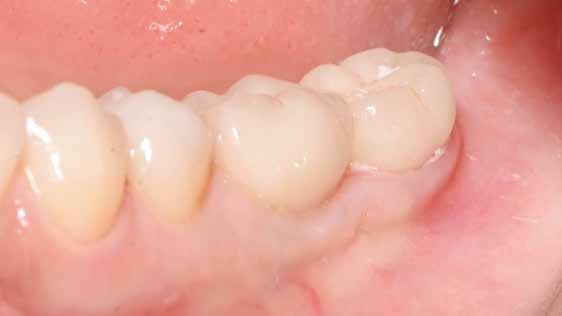

tottuk (az okklúziós koncepciók alapján az implantációs pótlások nem voltak vezető fogak, és csak könnyű érintkezéseket alakítottunk ki, amelyeket artikulációs papírral ellenőriztünk). A páciensek instrukciókat kaptak a megfelelő szájhigiénére vonatkozóan, összpontosítva a fogköz kefékkel történő tisztítására. Végső kontroll röntgenfelvétel készült. A PEEK felépítmény nem radioopák, így az implantátum és a korona közötti távolság könnyen meghatározható a röntgenfelvételen: a felépítmény megfelelően illeszkedik az implantátumban, ha az implantátum válla és a korona alsó széle közötti rés 0,55 mm a röntgenfelvételen (8–11. ábra)

Összegzés

Minden páciens elégedett volt a kezelés eredményével, a funkcionális és az esztétikai eredmény egyaránt kielégítő volt. Az egyetlen megjegyzés – a teljes kezelés hosszú időtartama – a felső állkapocs esetében volt. A meghosszabbított, öt hónapos csontintegrációs periódus miatt, a teljes

eljárás több mint hat hónapig tartott. A kezelő szemszögéből a gyártó szigorú előírásainak betartása mellett nem volt jelentős különbség a titánimplantátumok használatához képest. A felső és alsó állcsont fogainak pótlásában a CERALOG implantátumok megfelelő és stabil alternatívának tűnnek a titánimplantátumokkal szemben.